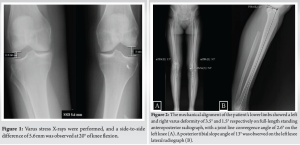

A 50-year-old female nurse presented with left knee instability. Two years prior, she suffered an ACL rupture at work, leading to discovery of an asymptomatic fibular head enchondroma which was confirmed by biopsy. However, as the enchondroma presented with endosteal scalloping, chondrosarcoma could not be excluded, and she underwent proximal fibular resection with FCL and biceps femoris repair with a suture anchor. Two-year post-surgery, she reported gross left knee instability with giving-way episodes, which occurred daily, even with walking. On physical examination, the affected knee had 20° excess hyperextension compared to the contralateral knee, 3+ anterior drawer, negative posterior drawer test, 3+ Lachman, and a 3+ pivot shift. In addition, dial test was symmetric at 30 and 90° flexion (the popliteus tendon was intact, and it is presumed that due to scarring the popliteofibular ligament had function), and 3+ instability to varus stress at 20° flexion and in full extension. This was confirmed with fluoroscopic varus stress views (Fig. 1). Neurovascular examination demonstrated no abnormalities. The affected extremity mechanical alignment was 3.5° varus compared to 1.5° varus on the unaffected limb on full-length standing anteroposterior radiograph. The mechanical lateral distal femoral angle of 88.8° was within normal limits as was the mechanical medial proximal tibial angle of 86.1°. Joint line convergence angle was 2.6°, suggesting that knee joint laxity was partly the cause of varus deformity (Fig. 2). ACL rupture and complete distal detachment of FCL and biceps femoris were confirmed by magnetic resonance imaging. There were no other concurrent ligamentous, meniscal, or chondral lesions (Fig. 3). Left knee ACL reconstruction using ipsilateral semitendinosus and gracilis hamstring (HS) autograft combined with revision PLC reconstruction using contralateral HS autograft was planned. In the absence of the proximal fibula, Pache’s technique was modified to fix both limbs of the graft onto the proximal tibia [15]. It was decided not to undertake an osteotomy as the deformity was <5°, there was no thrust on gait, and in conversation with the patient, she wished to avoid an osteotomy.